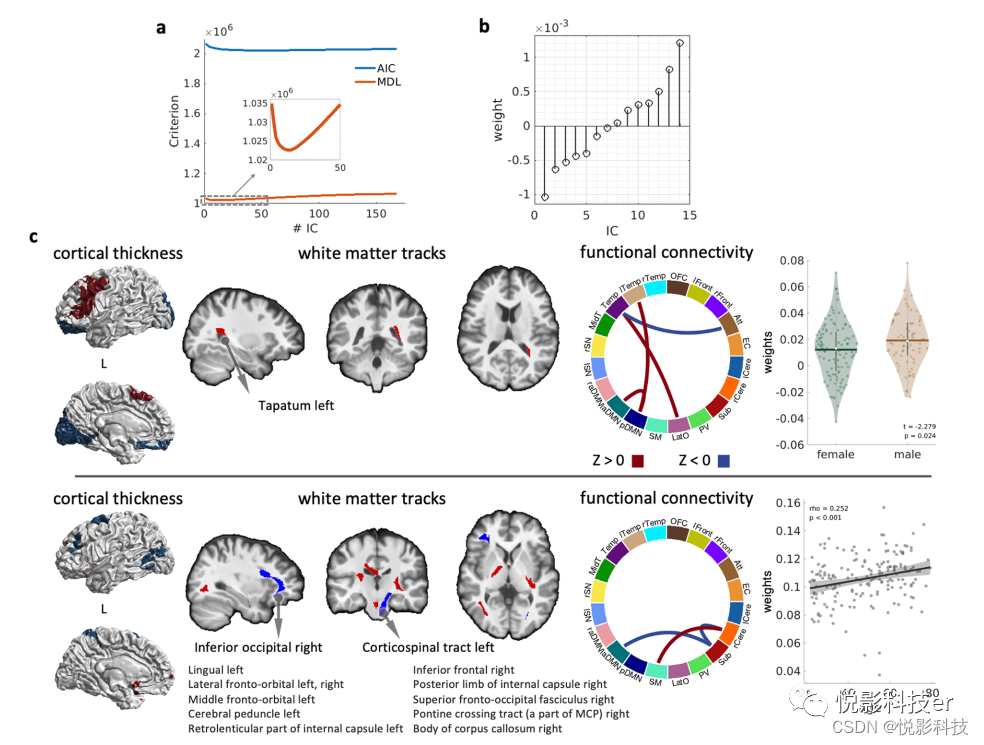

我们使用整合结构和功能图谱来检查大脑形态、功能网络和白质束的同步模式,这与性别和年龄有关。为此,我们采用联合独立成分分析(ICA)来结合结构和功能测量。对于功能数据,我们基于我们的20个功能网络计算网络级功能连接矩阵。对于结构t1加权数据,我们使用皮质厚度来表征皮质带。我们将年龄相适应的功能图谱映射到皮层表面,并计算每个功能网络的平均皮层厚度。根据HARDI图谱计算各白质束的平均GFA值。结果,多模态融合的输入矩阵包括34个厚度度量,来自白质包层的94个度量,以及210个功能连接,包括190个网络间功能连接和20个网络内功能连接,来自每个受试者的功能图谱。

我们根据赤池信息准则(AIC)和最小描述长度(MDL)估计选择了14个IC成分(图9a)。图9b显示了每个IC的负荷。然后,我们分别基于Pearson相关和t检验调查了这些组件的年龄和性别差异。图9c中最上面一排表示负负载最大的ICs。该成分的负荷未表现出显著的年龄相关变化,但表现出显著的性别差异。与性别相关的部分包括左额叶、眶额叶和初级视觉网络的皮层厚度,连接左颞叶的白质束,以及颞区与注意网络、后DMN和侧枕网络之间的功能连接。该成分可能反映了男性和女性在语言任务中大脑的不同招募。图9c中最下面的一排显示了正载荷最大的IC,显示了与年龄相关的显著增长(最后一张图的散点图)。这一与年龄相关的组成部分包括执行控制网络的皮层厚度、右侧小脑与感觉运动和皮层下网络之间的功能连接、皮层下与左前DMN之间的连接,以及连接皮层下小脑区域与大脑皮层的弥散白质束。该成分可能反映了皮层下和皮层间功能连接的年龄相关性变化。

图9 脑白质束皮层厚度、功能网络连通性和GFA的联合独立成分分析